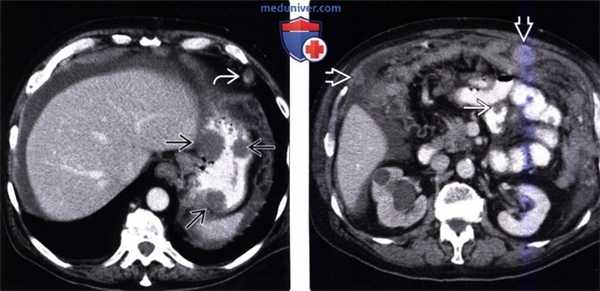

(Слева) На аксиальной КТ с контрастом у мужчины 69 лет, у которого ранее была обнаружена распространенная меланома, визуализируются типичные диссеминированные метастазы меланомы, вт. ч. в стенке желудка и лимфоузлах. Метастазы в стенке желудка могут изъязвляться, принимая вид «мишени» либо «бычьего глаза».

(Справа) На КТ у этого же пациента визуализируются распространенные метастазы, в т. ч. в тонкой кишке, лимфоузлах и сальнике в виде узлов и диффузного поражения этих органов. Определяется также обструкция правого мочеточника из-за его вторичного поражения.

(Слева) На аксиальной КТ с контрастным усилением у пациента с меланомой, у которого наблюдалось снижение веса и появилась диарея, визуализируются большие, изъязвленные образования в сочетании с аневризматическим расширением просвета тонкой кишки, в то же время, не определяется признаков тонкокишечной обструкции.

(Справа) На аксиальной КТ с контрастным усилением, выполненной женщине, у которой ранее был обнаружен рак молочной железы, определяется расширение желудка и двенадцатиперстной кишки с резким сужением просвета ее третьей части, обусловленное образованием в стенке. Во время операции был подтвержден метастаз рака молочной железы.